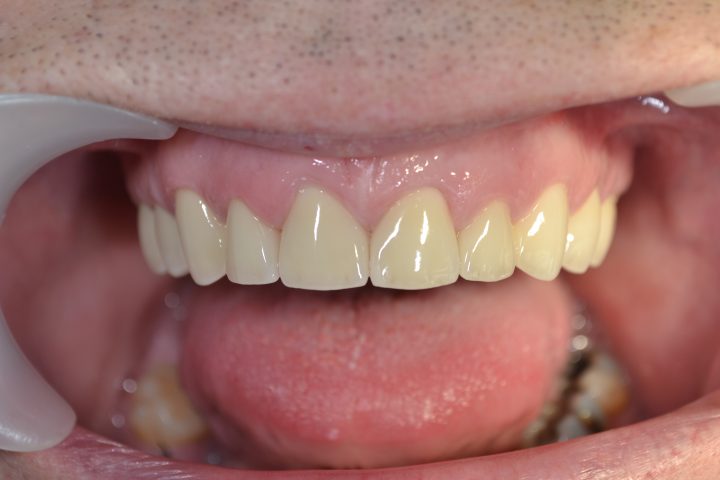

So, nach der 14 Wochen langen Heilungszeit, im Oktober 2017ist er zweites Mal nach Budapest geflogen, wann er oben und unten insgesamt 28 Stück metallfreie Zirkon Kronen im Ablauf 12 Tagen bekommen hat.

Peter macht noch immer Drachenflieger, aber trägt immer Zahnschienen zum Fliegen.